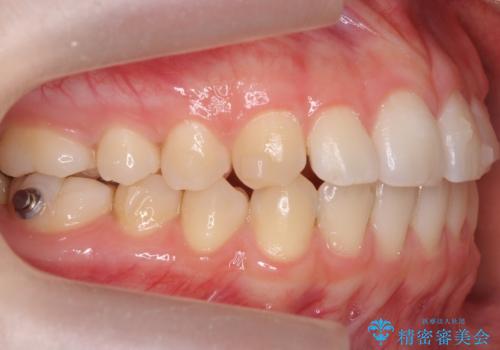

咬んでも前歯が閉じない 矯正治療で見た目を含めて改善

咬んでも向こう側が見える、前歯が閉じない症状でした。また、上の前歯が少し前に出ている状態でした。

上の前歯をわずかに削る処置を行い、後ろに下げながら下の歯となるべく咬むように矯正治療を行いました。

治療前に、患者様が矯正ではなくセラミッククラウンで前歯をかぶせる治療についても気にされてました。

歯の位置が悪く、下の歯と咬まない為咬ませようとすると長い歯になる上に、神経をとらないとひっこめることが難しいと説明を行い、矯正治療をおすすめし、行うこととなりました。